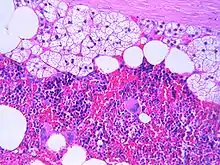

| An adrenal myelolipoma | |

The typical microscopic features of myelolipomas are shown in the image. There is a mixture of normal adrenal tissue, fat, and a full trilineage maturation of the three major blood-forming elements: myeloid (white blood cell forming), erythroid (red blood cell forming), and megakaryocytic (platelet forming) lines.[1]